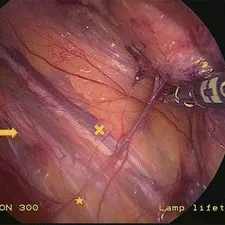

Športnikova kila je izraz za bolečinski sindrom v dimljah, ki je precej kompleksen tako glede diagnostike, kot samega zdravljenja.

Razlogov za bolečino v dimljah je veliko, lahko gre za pravo kilo, ki se vidi kot izboklina iz trebuha ob napenjanju, pogosti vzroki so lahko okvare hrbtenice, pri katerih bolečina pasasto seva v dimlja, možni pa so tudi razni urološki vzroki.